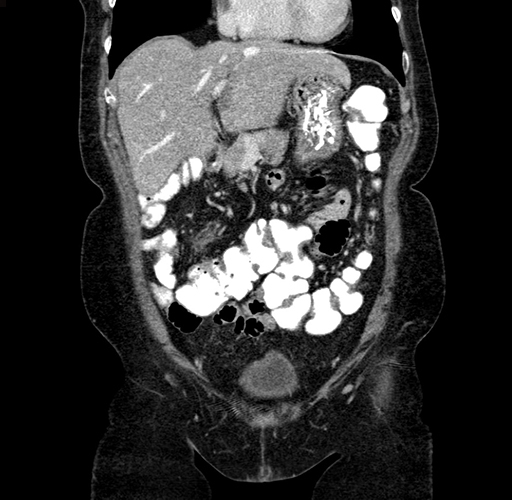

Pre-Chemo: Coronal Venous